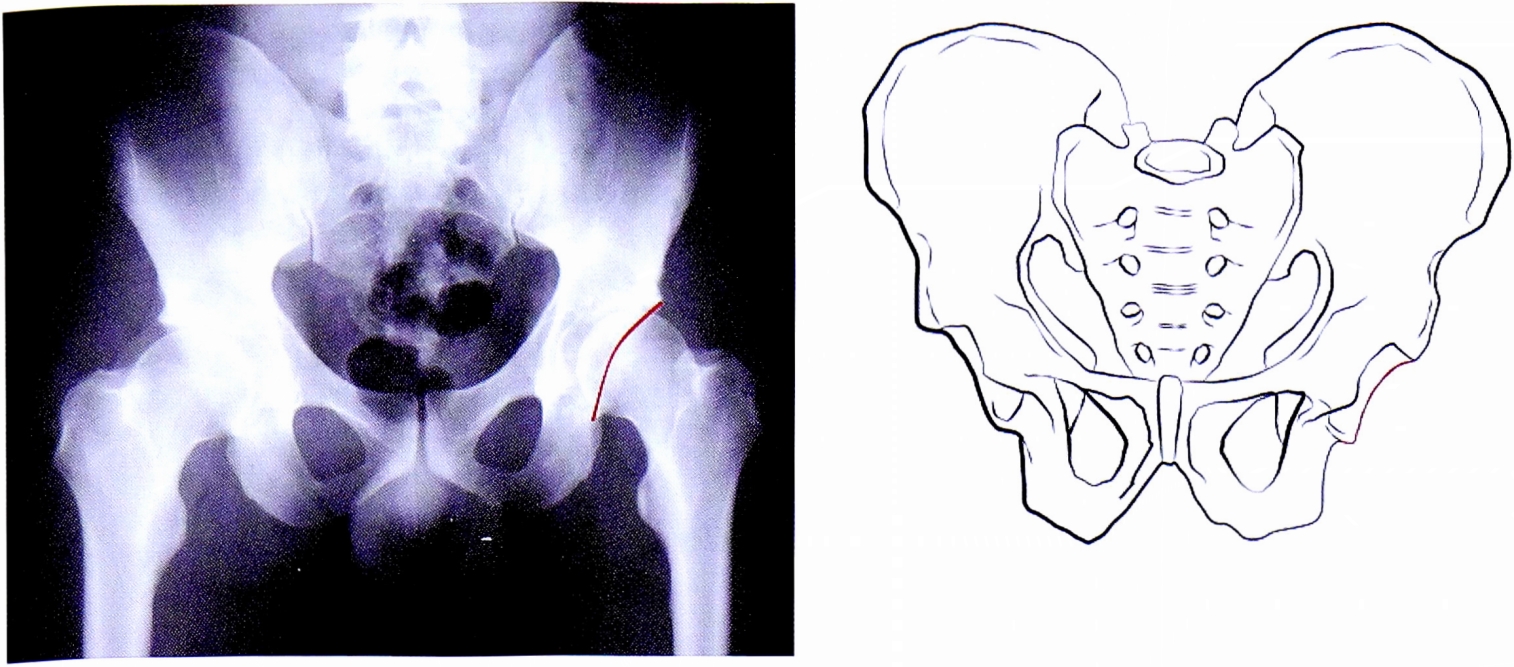

- Подвздошно-гребешковая линия (соответствует терминальной линии тазового кольца) в передних отделах соответствует передней колонне вертлужной впадины, в задних отделах она отражает тело подвздошной кости на протяжении до крестца — в норме она непрерывна (рис. 1). С клинической точки зрения целостность тазового кольца определяет непрерывность подвздошно-гребешковой линии.

Рис. 1. Подвздошно-гребешковая линия на рентгенограмме и на схематическом изображении таза.

Fig. 1. Ileopectineal line on AP pelvic X-ray and on schematic pelvis.